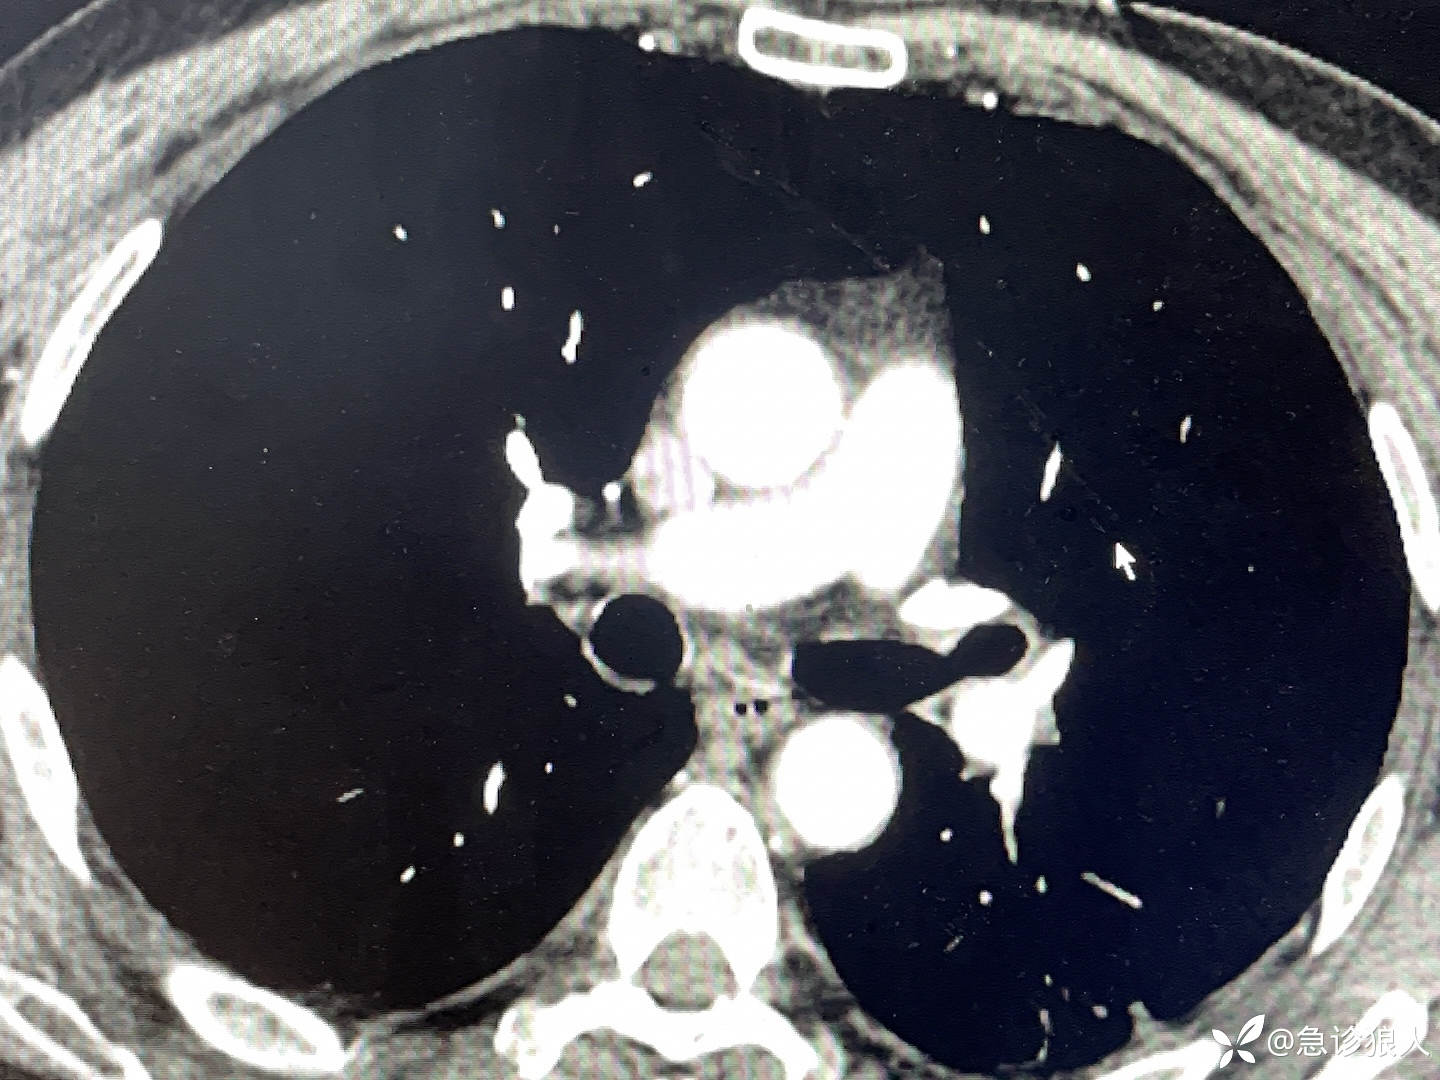

“昨晚10点看急诊门诊,一下寒颤,不行了,转来了抢救室,他们怀疑肺栓塞,做了肺动脉CTA,没事!现在血压多巴胺维持不住。”

3、这么年轻,能正常进食,出现这种情况,一般会有诱因,最常见的诱因就是感染。腹痛、发热寒颤,进展如此快,最常见的是胆总管出事了!看CT,血检胆红素、转氨酶、淀粉酶全正常,电话肝胆外科,直接排除!但是胆囊周围确实有液体!

4、在等复查血结果的时候,反复的看患者的CT!感觉这个ct太熟了!曾经好多不眠夜看到过!细看CT!双肾周都有渗出,合情合理怀疑肾脏出事了!再细看,肾无低密度灶,排除肾脏感染!肾盂、舒尿管不扩张,没有结石感染!膀胱里没有高密度灶,不存在排石感染!更可气的!尿常规虽然白细胞3个+,但不至于出现这个情况!

这个影像真的太熟了!我曾经还写过!

我提高语速,“重症感染,没找到感染灶,我能看出来的就两个事,胆囊周围渗出增多,但不像胆囊,双肾周围渗出增多,但我顺着看了好几遍,泌尿系我没看到问题!”